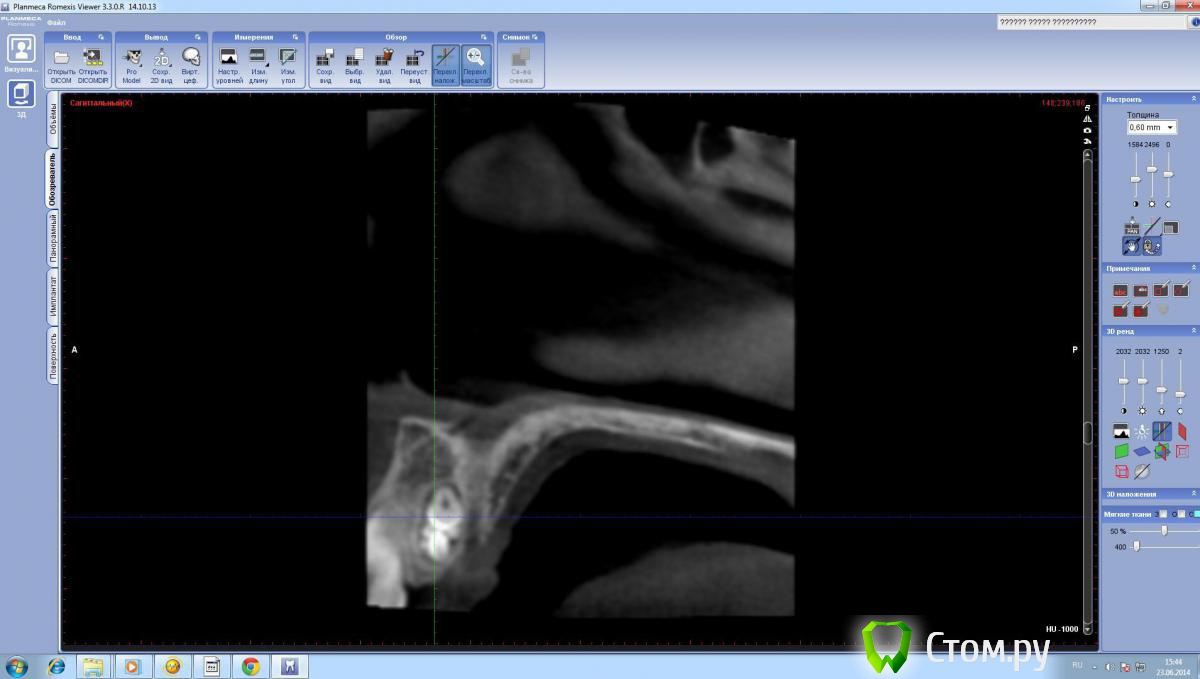

SergeiVar Опубликовано 30 июня, 2014 Поделиться Опубликовано 30 июня, 2014 (изменено) Пациентке 11 лет. Направлена ортодонтом на удаление сверхкомплактного 21 зуба. жалоб никаких нет. На 3д в крипте несколько зачатков зубов. Небным доступом достал 4 штуки, остальное в отсос попало. Затрудняюсь с диагнозом. На одонтому не похоже, скорее аномалия зачатка. (один зуб, остальное как эмалевые капли). Изменено 30 июня, 2014 пользователем SergeiVar Ссылка на комментарий

dr-krasnov Опубликовано 30 июня, 2014 Поделиться Опубликовано 30 июня, 2014 Составная одонтома. 5 Ссылка на комментарий